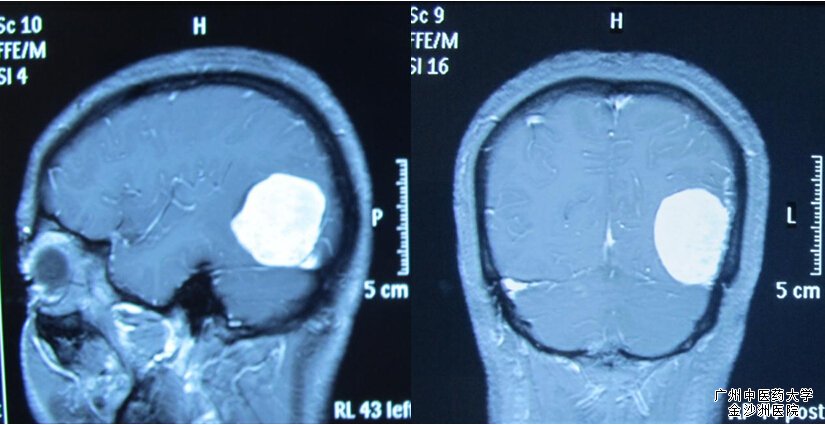

病人为何术后突然昏迷,回顾病史在患者入院初始,手术主刀周强教授带领团队对患者病情、手术方案及手术注意事项展开了术前讨论:病人颅内肿瘤位于左小脑幕及左侧颞枕,并紧贴左侧横窦,手术非常容易损伤这条较大的回流静脉;但一旦损伤即可能造成大量出血而致患者术中休克死亡;且肿瘤靠近大脑颞叶运动语言中枢,以及枕部的视觉中枢,术中若有丝毫操作损伤到该区域,患者术后就可能出现偏瘫失语、双目失明等后遗症。术前准备就绪后于8月5日上午10点在全麻下行左颞枕开颅肿瘤全切除术(显微手术),手术顺利完成;由于在术中发现患者脑血管畸形且血管较脆、弹性差、较难止血,因此周强教授反复叮嘱术后必须高度警惕有出现颅内出血的危险。

术前MRI

手术镜下肿瘤全切